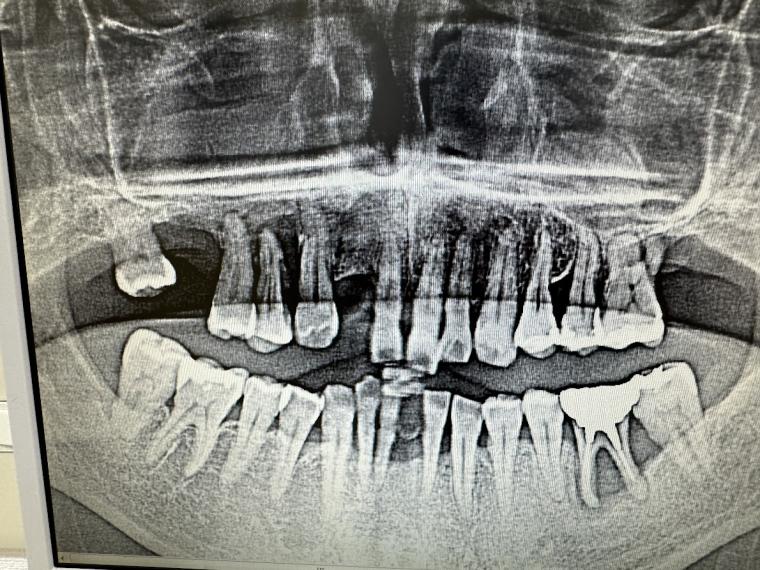

(2026年)

その影響もあり、気づかないうちに

歯がだいぶ抜け、骨もなくなってしまいました。